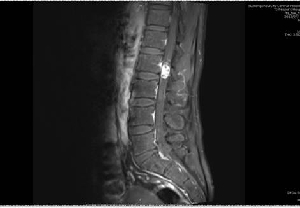

我院神經(jīng)外科顯微鏡下成功切除椎管內(nèi)腫瘤1例

日前,神經(jīng)外二科成功為一名腰2椎管內(nèi)占位性病變患者實(shí)施了顯微鏡下椎管內(nèi)病變切除術(shù),術(shù)后患者癥狀完全改善。患者李某,男,40歲,因“右下肢疼痛、麻木8年余,伴腰